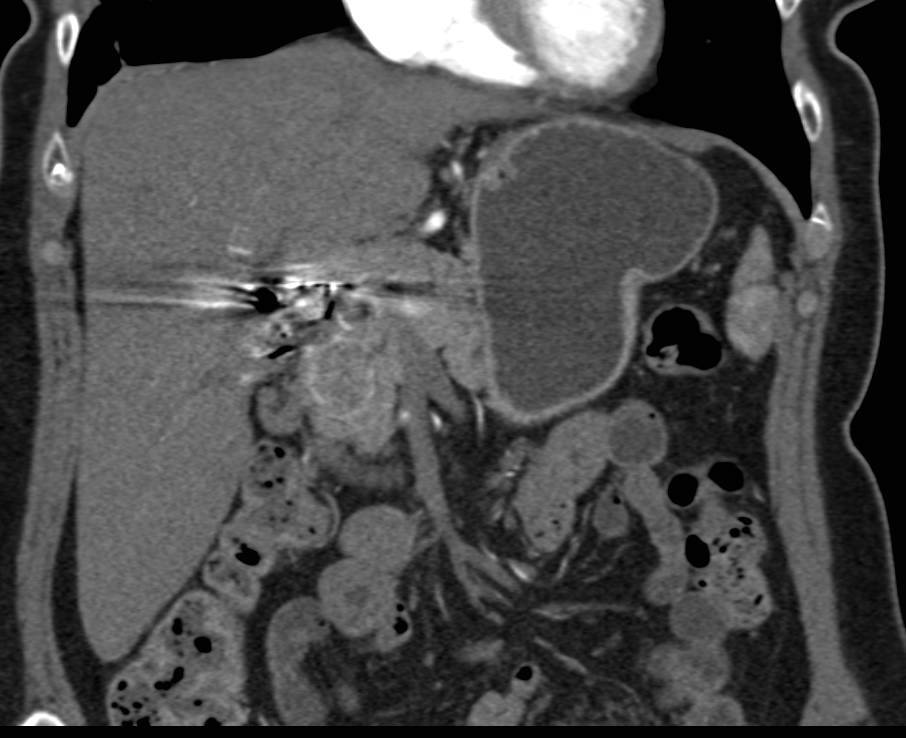

Pancreatic Necrosis with Pancreatic Abscess